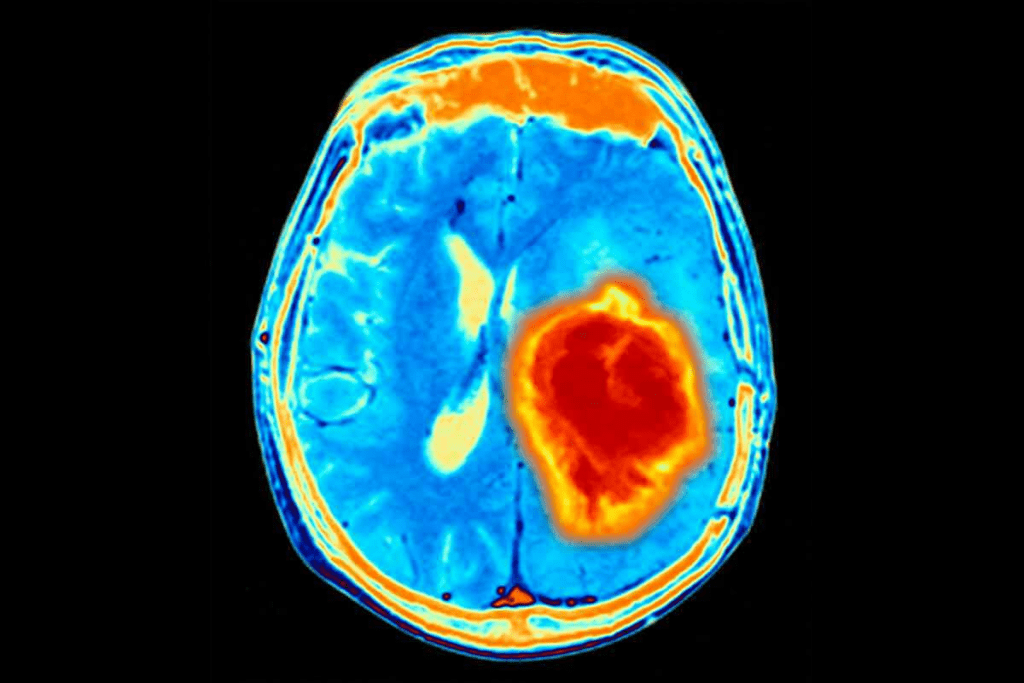

What Do Tumors Look Like on MRI? Visual Characteristics

On MRI, tumors show unique patterns and abnormalities. MRI technology gives detailed views of soft body tissues. It’s key for spotting tumors.

Signal Intensity Patterns and Abnormal Masses

Tumors on MRI look like distinct masses with odd signal intensity. The intensity changes based on the tumor type, grade, and makeup. For example, some tumors look bright on T2-weighted images because they have lots of water. Others look dark on T1-weighted images.

Edema, Enhancement, and Other Visual Markers

Swelling, or edema, around tumors is common on MRI. It shows up as a bright area on T2-weighted images. Tumors also show contrast material uptake, which helps figure out their nature and grade.

Other signs include the tumor’s shape, its position, and any effects it has on nearby areas. These details help doctors decide if the tumor can be removed and plan treatment.

Case Examples of Different Tumor Appearances

Different tumors look different on MRI. For instance, glioblastomas are irregular and enhance with contrast, surrounded by swelling. Meningiomas, on the other hand, are well-defined and enhance near the brain’s surface.

Studies show MRI can tell apart various brain tumors by their looks. This info is essential for making treatment plans and predicting how patients will do.

Benign vs. Malignant Brain Tumor MRI: Critical Differences

It’s important to know the difference between benign and malignant brain tumors on MRI. MRI scans help doctors tell these tumors apart. They look at specific signs in the images.

Well-Defined Borders vs. Invasive Patterns

Benign tumors have well-defined borders. They look like clear, round shapes that stand out from the brain. Malignant tumors, on the other hand, have invasive patterns. Their edges are not clear and blend into the brain.

“Benign tumors have clear edges, while malignant ones don’t,” a study on brain tumors says.

Contrast Enhancement Characteristics

How tumors look with contrast on MRI is key. Malignant tumors show heterogeneous enhancement. They have spots of dead tissue and uneven brightness. Benign tumors, by contrast, look homogeneous. They are evenly bright and uniform.

- Malignant tumors: heterogeneous enhancement, necrosis, irregular patterns

- Benign tumors: homogeneous enhancement, uniform patterns

Growth Patterns and Surrounding Tissue Effects

The way a tumor grows and affects the brain is also telling. Malignant tumors infiltrate the brain, causing swelling and pressure. Benign tumors can also cause swelling but tend to displace brain structures instead of spreading into them.

A top neuroradiologist says, “MRI shows how aggressive a tumor is. It helps doctors decide the best treatment.”

In summary, MRI is key in telling benign from malignant brain tumors. By looking at the tumor’s edges, how it looks with contrast, and how it grows, doctors can make better diagnoses and plans.